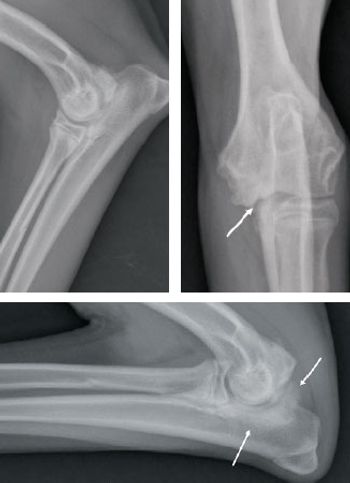

Raleigh, N.C. - A veterinary team at North Carolina State University recently performed a unique total knee replacement surgery on a cat.